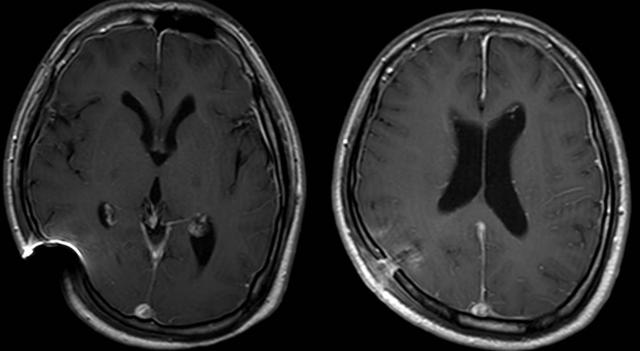

2019-03-02 出院前头颅MRI

在医护人员的精心呵护下,李刚日渐好转,精神一天比一天好起来,更令人欣喜的是,医生们发现李刚原先梗阻的分流泵居然逐渐恢复了正常的弹性,这表明他颅内感染已经完全治愈,同时分流管的再通也表明李刚可以免于针对脑积水的再次手术治疗!李刚于2月18日拔出了头部的引流管,他终于可以在床上慢慢的坐起来,可以慢慢下床扶着床栏走几步,可以在家人的帮助下自己洗漱、自己如厕,可以不用任何人帮忙自己在病区里散步……现在他俨然像个没生过病的健康人了。任铭主任说,李刚再复查下核磁,没有问题就可以出院回家了。这句话,李刚一家人盼了三个多月,李刚父母更是高兴的不知道说什么好。